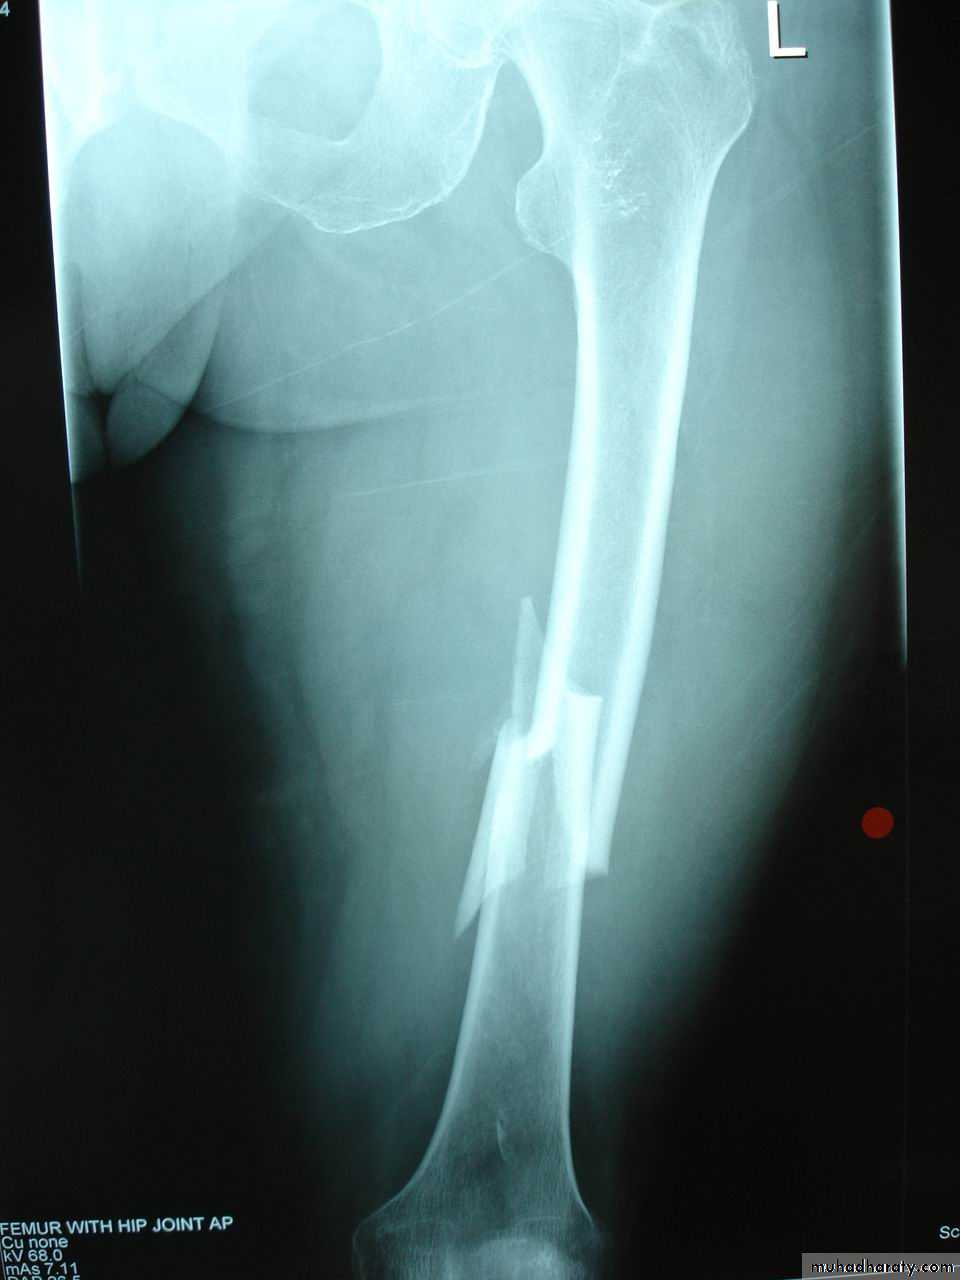

6Segmental fracture

The bone is fractured at more than one level